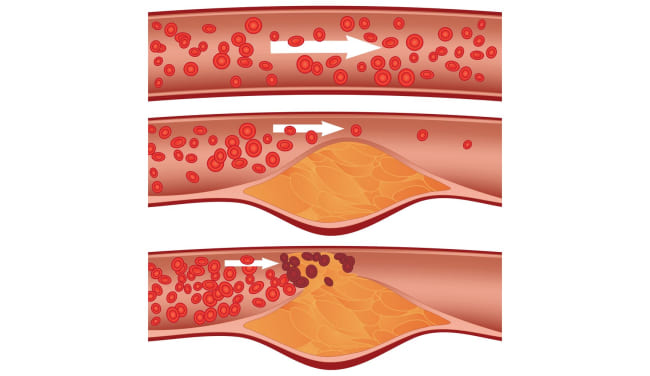

Semua orang tahu bahwa kolesterol itu buruk. Dialah yang menyumbat pembuluh darah kita, menyempitkannya, dan mengganggu sirkulasi darah. Tapi itu bukan satu-satunya penyebab, bukan?

Kolesterol

Ya, Anda benar. Plak kolesterol atau "plak aterosklerotik" menyumbang sekitar 65-70% dari kontaminasi vaskular.

Pada usia 50 tahun, hingga 5 kg plak kolesterol terakumulasi dalam pembuluh darah seseorang. Endapan kolesterol menyempitkan lumen pembuluh darah 4-5 kali.

Bayangkan. Jika lumen normal wadah adalah jari Anda, maka 5 kg plak kolesterol mengurangi lumen menjadi ukuran 4 korek api.

Plak kolesterol sendiri tidak mengancam jiwa. Ya, kualitas hidup menurun, tekanan meningkat, ada sakit kepala dan nyeri sendi, kelemahan, dan apatis. Yang jauh lebih berbahaya adalah massa trombotik dan kristal kalsium, yang juga terakumulasi dalam pembuluh darah kita.